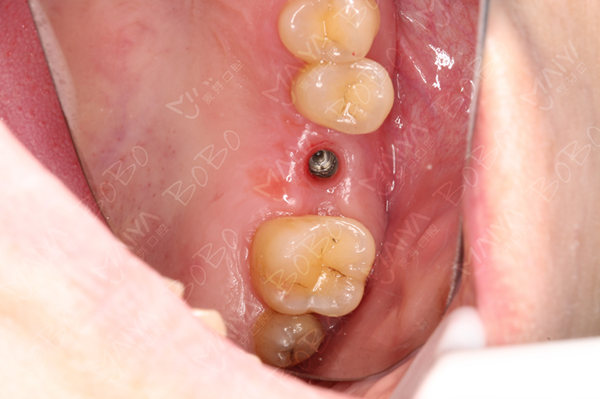

种牙过程中

种植体的植入